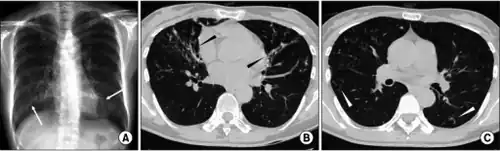

| Fibrothorax caused by infection with M lentiflavum. | |